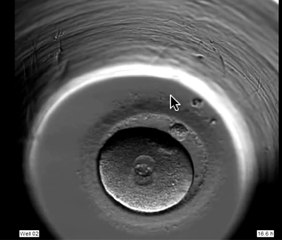

A major fertility group has incorrectly transferred the wrong embryo to a patient. It's the second incident that Monash IVF has apologised for in recent months.